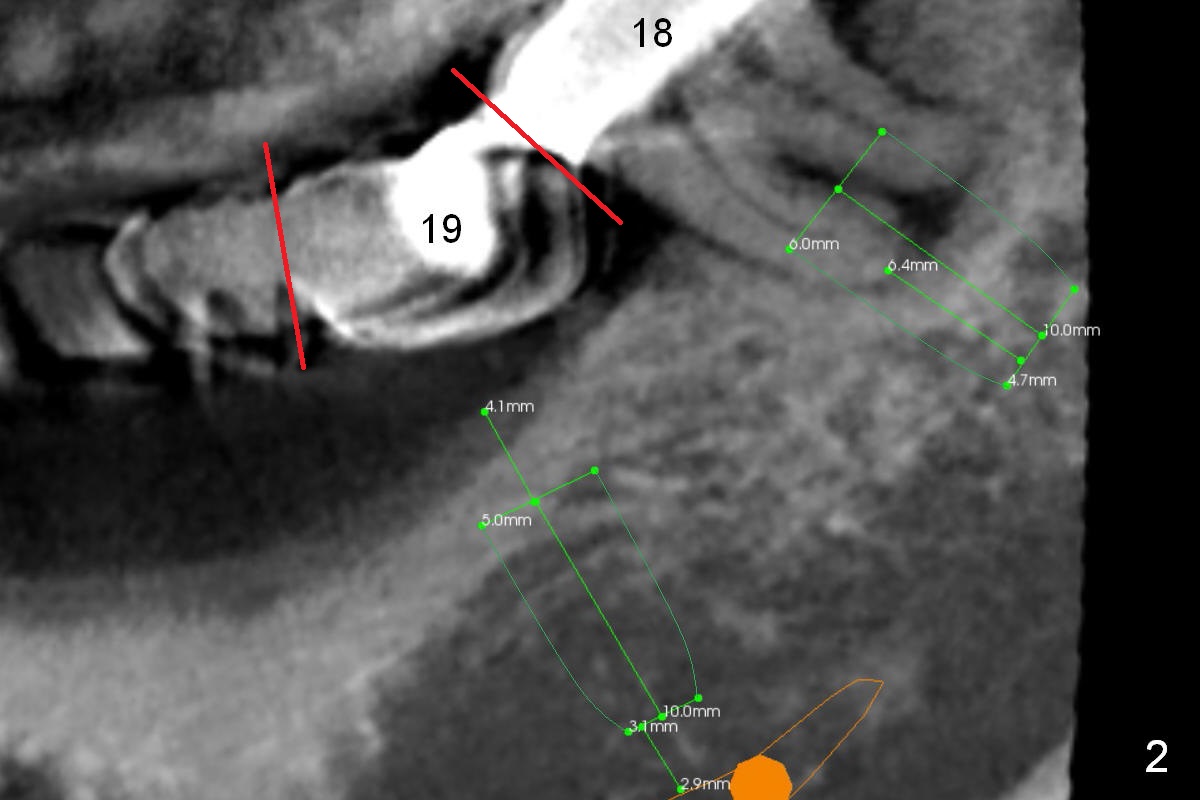

The abutment tooth at #18 is symptomatic with gingival recession (Fig.2). It appears that it is overloaded due to pressure from the tooth #14 (Fig.1 arrow). An implant at #19 should be able to alleviate the pressure on the tooth #18.

The 3-unit bridge (#18-20 in Fig.1) will be sectioned (Fig.2 red lines) with the pontic of #19 to be removed. The ridge top is narrow (Fig.3). To place a 5 mm UF implant, the triangular ridge top should be reduced (result).